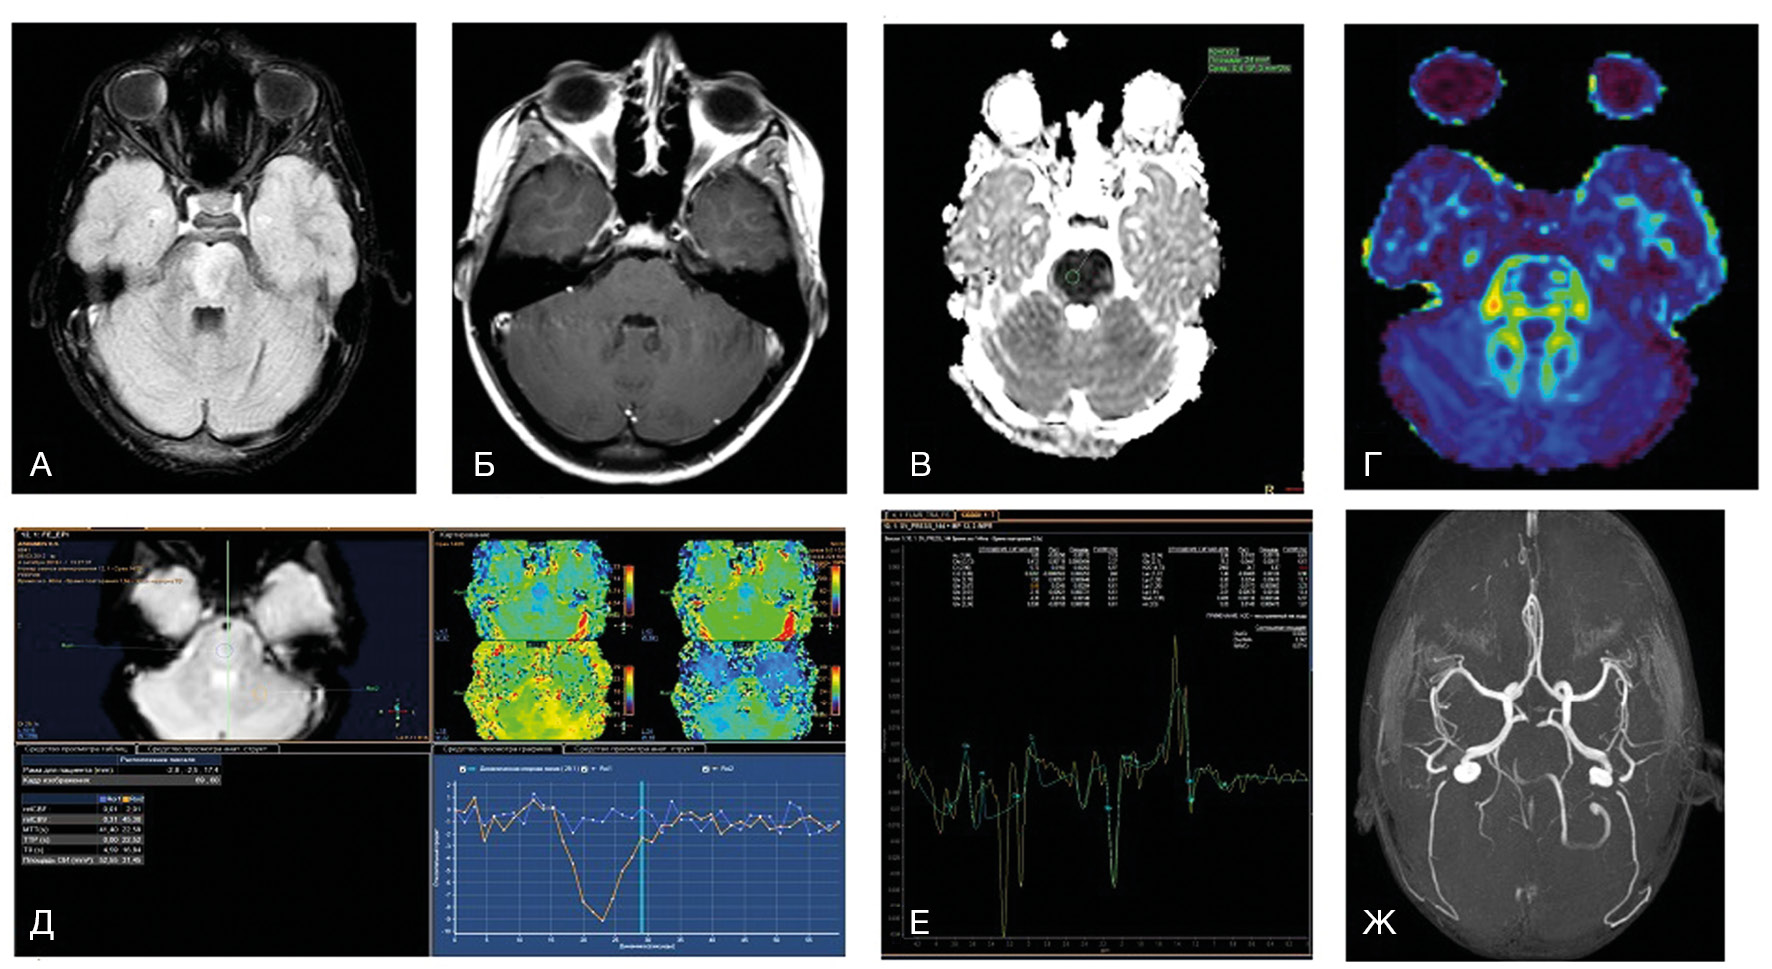

МРТ-признаками глиомы ствола мозга являются Т2-гиперинтенсивные очаги с масс-эффектом, окружающие цистерны, 4-й желудочек, сильвиев водопровод и/или мозжечок. Чаще всего у детей развиваются отличающиеся по анатомии и клиническому течению 3 группы глиом ствола — это диффузная внутренняя понтинная глиома, экзофитическая среднемозговая глиома и тектальная глиома [70]. Первый вариант имеет наихудший прогноз выживаемости (около 1 года) [71]. На МРТ отличительными особенностями являются перифокальный отек, отсутствие накопления контраста и масс-эффекта. Чаще всего возникает в возрасте 5–10 лет с развитием клинической триады — атаксии, поражения черепно-мозговых нервов и длинных трактов. В типичном случае поражение тотальное или субтотальное, чаще всего в мосту. Хотя отсутствие накопления контраста является характерной особенностью, в некоторых случаях наблюдается негомогенное частичное или периферическое накопление парамагнетика [72].

У детей младше 3 лет могут возникать солидные примитивные нейроэктодермальные опухоли. Они фокально, экзофитно расположены обычно в мосту, умеренно накапливают контраст и часто распространяются субарахноидально [73–75]. Опухоли ствола у детей также могут развиваться при неврофиброматозе 1-го типа [76, 77]. Чаще всего возникает астроцитома, которая растет менее агрессивно, чем у детей без неврофиброматоза [78]. У таких пациентов выявляются яркие Т2-гиперинтенсивные очаги, которые остаются стабильными и иногда исчезают у пациентов старше 12 лет [79]. Интракраниальное поражение ствола мозга может развиваться при гистиоцитозе клеток Лангерганса [80, 81]. Это редкое гранулематозное заболевание системы моноцит-макрофаг. Типичные клинические проявления при этом — литические очаги краниофациального скелета, вовлечение гипоталамически-питуитарной области, несахарный диабет. Интракраниально выявляются симметричные Т2-гиперинтенсивные очаги нейродегенерации и реже регистрируются массивные туморозные очаги [82].